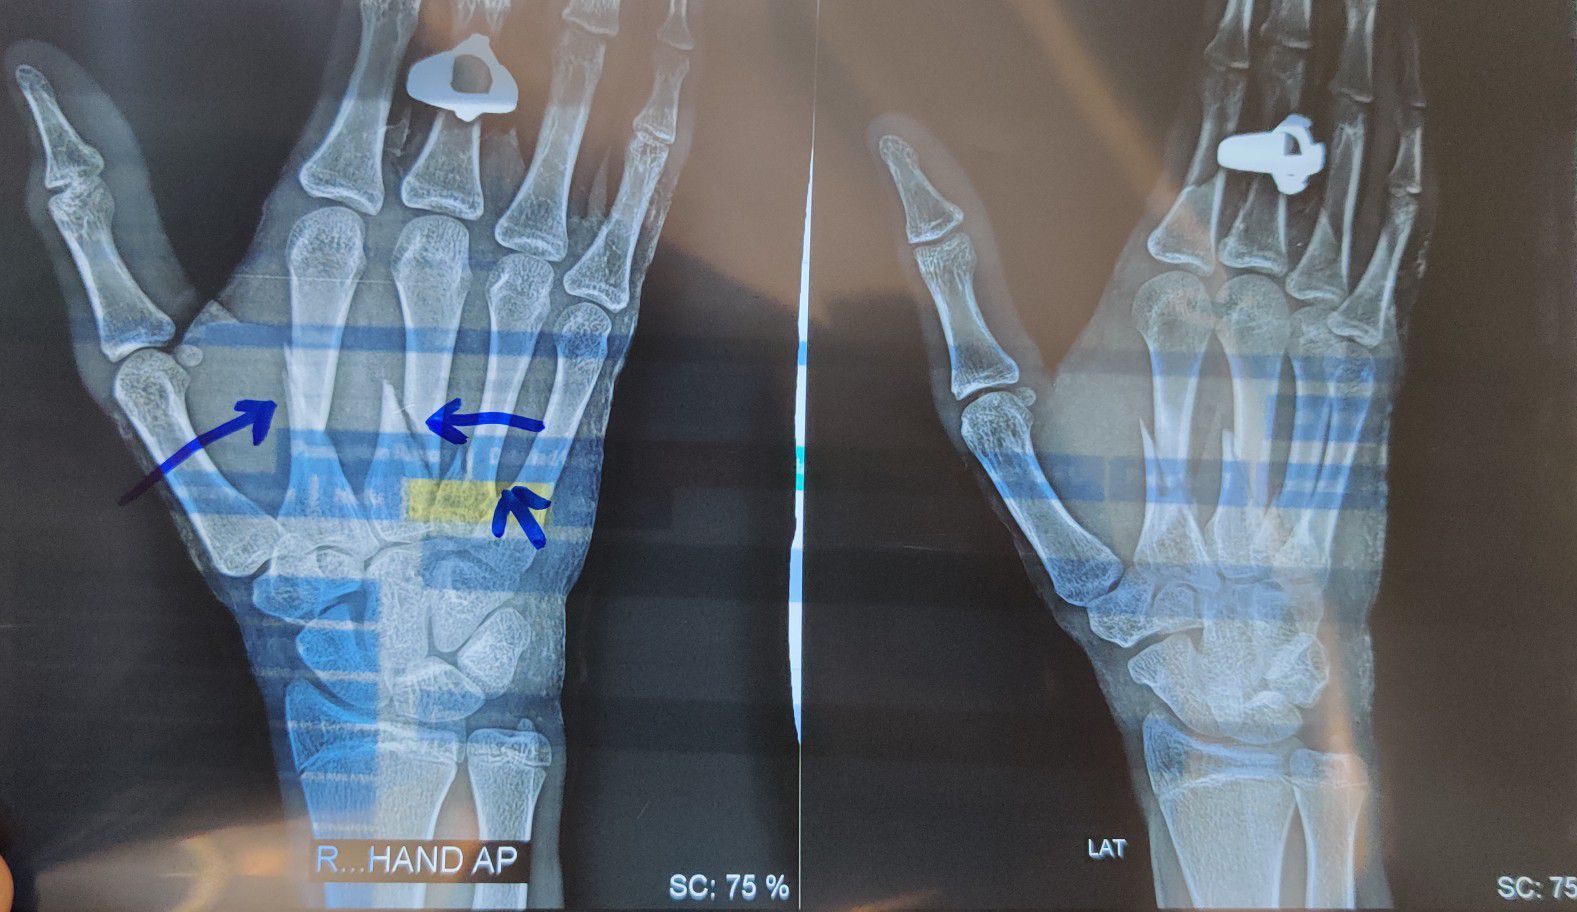

Fracture 2nd 3rd and 4th Metacarpal

Xray

Fracture

Hand